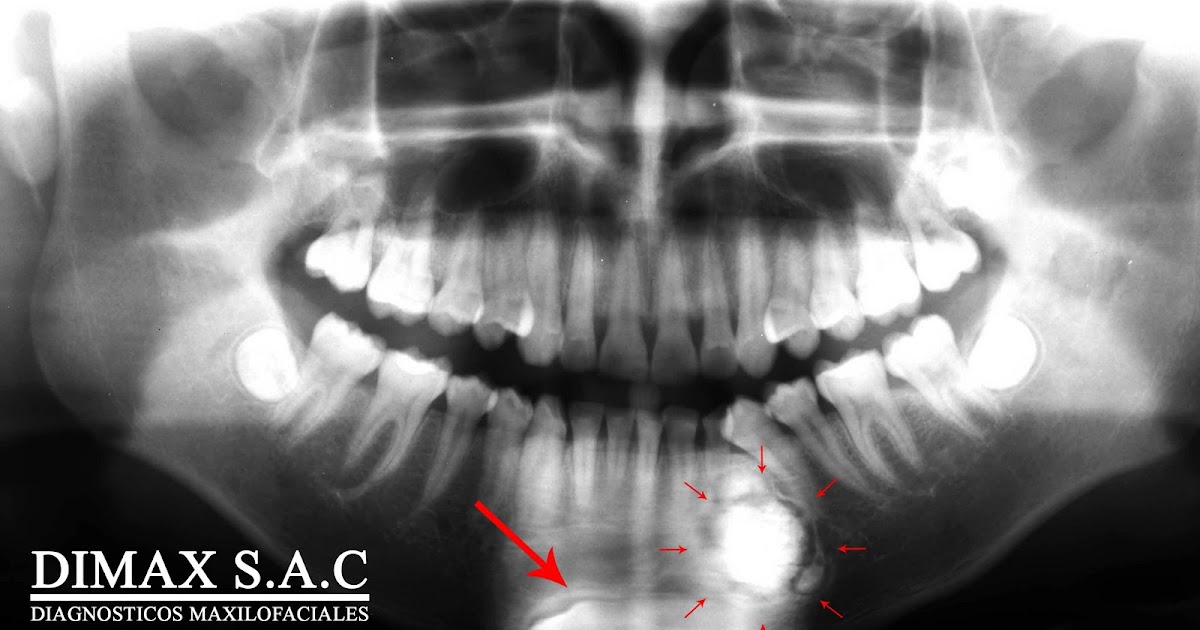

From dimax-sac.blogspot.com

DIAGNOSTICOS POR IMAGENES Odontoma Compuesto 01 Ada Code For Odontoma    in conclusion, the presence of odontoma in association with the.  before coding any incision and drainage, it is necessary to have the most current copy of the ada’s cdt manual, the ama’s cpt manual and the two.  diagnosis of odontoma at an early age and its surgical excision may prevent eruption disturbances.  d7250 is the appropriate. Ada Code For Odontoma.